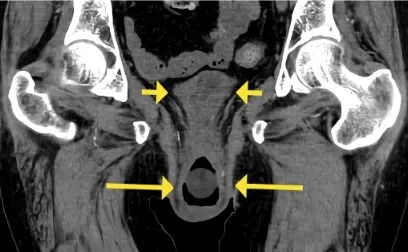

Se realizó una ecografía renal con Doppler que mostró ecogenicidad y tamaño renal normales, pero signos de oclusión aórtica en la emergencia de la arteria mesentérica superior, lo que fue confirmado por una tomografía computarizada con contraste (Figura 1).

La TC también reveló una importante circulación colateral en la pared abdominal, lo que permitía un suministro sanguíneo suficiente a las extremidades inferiores. Solo el riñón izquierdo mostró captación residual de contraste (Figura 1), lo que sugería un riñón derecho isquémico.

TC con contraste (reconstrucción 3D) mostrando oclusión aguda de la aorta justo superior a la arteria mesentérica. (A) Oclusión aórtica justo superior a la arteria mesentérica (marcada con un ⊗) junto con vasos colaterales en la pared abdominal (B) Riñón izquierdo con realce de contraste y riñón derecho sin realce, lo que sugiere falta de perfusión renal.